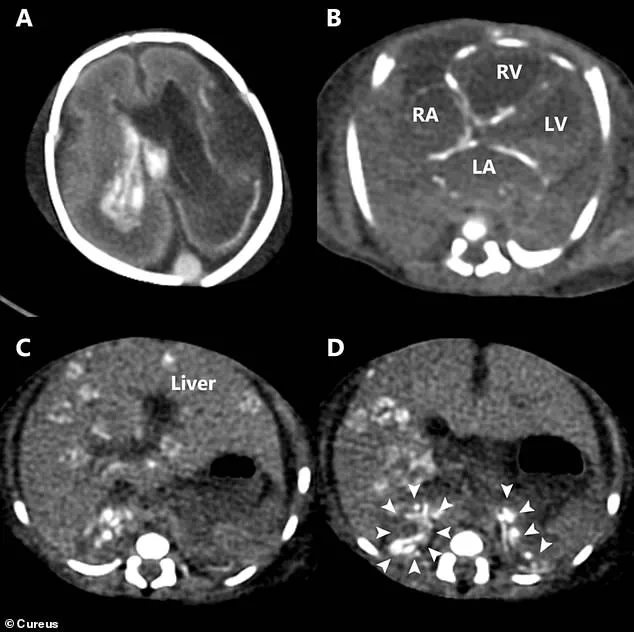

These images from a scan after the baby's death show how the herpes infection caused catastrophic damage throughout his entire body.

A) Bleeding inside the brain's fluid-filled chambers (ventricles).

One chamber is also enlarged.

B) Abnormal, dense spots (calcifications) are visible in the walls of the heart's chambers.

C) Widespread, round, dense spots throughout the liver, indicating tissue damage.

D) Heavy, dense areas in both of the small adrenal glands (located on top of the kidneys), showing they were also severely affected.

A post-mortem CT scan provided the final confirmation of the infection's destructive path.

The post-mortem CT scan revealed multiple areas of overload of calcium in his tissue, a sign of severe, chronic inflammation, throughout the walls of his heart, liver and adrenal glands.

There was bleeding into the fluid-filled spaces, ventricles, within his brain.

Specifically, the case report noted the bleeding due to its inability to clot was in the left lateral and third ventricles, confirming a disseminated HSV infection that began in the womb.